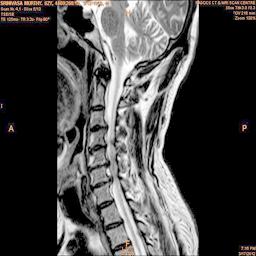

The proposed algorithm uses HSV color space to enhance spinal cord images since this color space offers many advantages such as color separation from intensity, reduced color distortion and efficient enhancement. The algorithm proposed takes advantage of this color space by performing enhancment operation on the intensity or value component and preserving the color information. The first column of Fig. 3 shows the original spinal cord test images followed by the extraction of value component presented in second column. Next, the third column of Fig. 3 shows the value component enhanced using the proposed multirate multiscale retinex algorithm. The modified version of the retinex algorithm presented here is capable of producing high quality reconstructed pictures, far better than the other researchers method.

The developed algorithm presented in the previous section was coded using Matlab Version 8.0. The experiment was conducted by considering poor quality spinal cord images of having various lesions. The first column of Fig. 4 shows the axial view of neck spinal cord images of size pixels, respectively. The second column of Fig. 4 presents the same images enhanced using histogram equalization. As is evident from the results presented, the histogram equalization method performs global image enhancement operation which improves the contrast of an image but at the cost loss in image details. The third column of Fig. 4 shows the MSR based spinal cord image enhancement. It can be seen that from the result presented, MSR scheme improves the details that are not clearly visible in histogram equalization technique. In general, image enhancement achieved by MSR method is better compared to histogram equalization. However, the MSR method voilates gray world assumption. Therefore, the image enhanced by this scheme appears to be grayish. Although, numerous work have been reported for solving the problem due to gray world voilation, no work seems to developed for complete elimination.

The fourth column of Fig. 4 shows the image enhanced using Chao et al. []. It can be seen from the results presented that the reconstructed images of Chao’s method have black spots. The appearance of these dark patches degrades the visual quality of the enhanced image. The image enhanced using proposed multirate multiscale retinex image enhancement method presented in the fifth column of Fig. 4, overcomes the drawback of the Chao’s method. As we can see from the simulation results, image enhancement achieved by the proposed method has improved details with significant contrast enhancement. The enhanced images from the proposed method provides information to physicians, radiologists and researchers for various types of pathology detection.